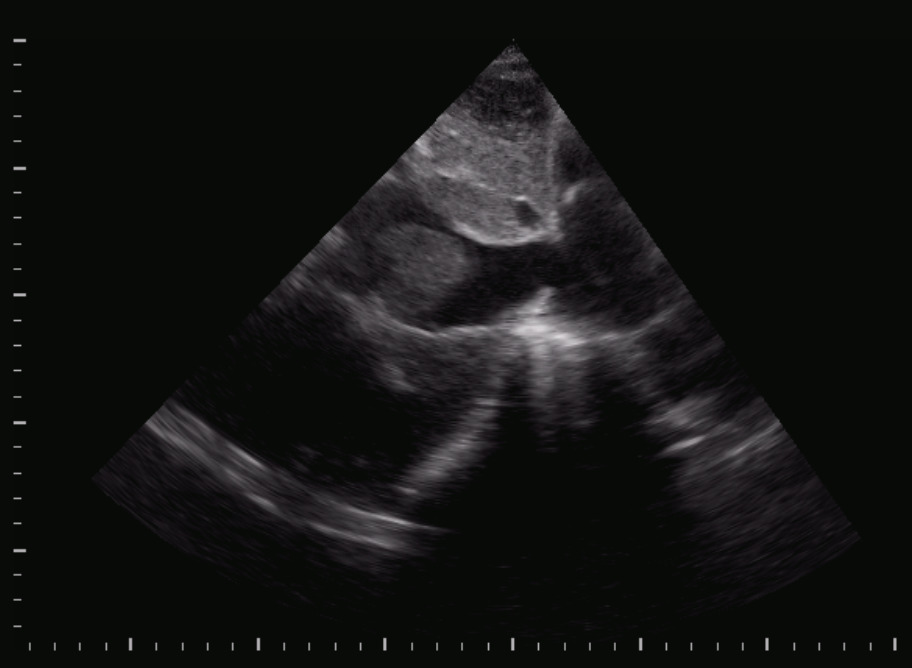

Titolo:

Ostruzione dinamica dell’efflusso VSx

Autore:

Laura Massironi